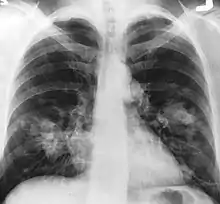

Le cancer du poumon peut être vu sur les radiographies thoraciques et le scanner. Le diagnostic est confirmé par une biopsie. Ceci se fait généralement par bronchoscopie, ou par biopsie guidée par scanner. Le traitement et le pronostic dépendent du type histologique du cancer, de son stade (degré de dissémination), et de l'état général de santé du patient.

La radiographie thoracique est la première mesure à prendre si un patient se plaint de symptômes pouvant suggérer un cancer du poumon. Ceci peut révéler une masse évidente, un élargissement du médiastin (qui suggère une extension aux ganglions lymphatiques qui s'y trouvent), une atélectasie (affaissement), une inflammation (pneumonie) ou un épanchement pleural. En l'absence de signes radiographiques, mais si les soupçons sont élevés (par exemple, un gros fumeur avec hémoptysie), une bronchoscopie ou un scanner peuvent donner l'information nécessaire. La bronchoscopie ou la biopsie guidée par scanner sont souvent utilisées pour identifier le type de tumeur[3].

Le diagnostic différentiel pour les patients qui présentent des anomalies de la radiographie thoracique consiste à distinguer le cancer du poumon des maladies non malignes. Ces dernières peuvent être des infections, telles que la tuberculose ou la pneumonie, ou des inflammations comme la sarcoïdose. Ces maladies peuvent donner lieu à des lymphadénopathies du médiastin, ou à des nodules du poumon, qui peuvent imiter des cancers du poumon[4]. Le cancer du poumon peut par contre être une trouvaille incidentelle : un nodule pulmonaire solitaire (lésion en « pièce de monnaie ») vu sur une radiographie du thorax ou un scanner pris pour une tout autre raison.